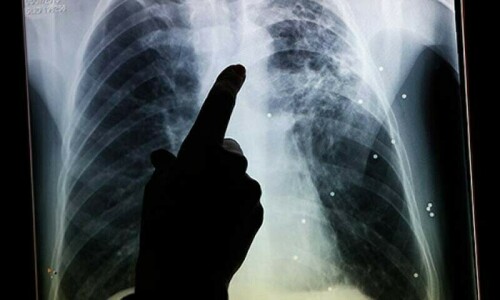

ISLAMABAD: While World Tuberculosis (TB) Day will be observed today with the theme ‘Yes We Can End TB’, the cases of drug-resistant TB in Pakistan are going to become a major challenge as “75pc of them are not identified”.

With Pakistan ranking fifth among high-burden countries globally, the country witnesses approximately 608,000 new TB cases and 15,000 drug-resistant TB cases annually.

However, international non-government organisation Doctors Without Borders (MSF) has claimed that over 75 per cent of drug resistant tuberculosis cases were not identified in Pakistan.